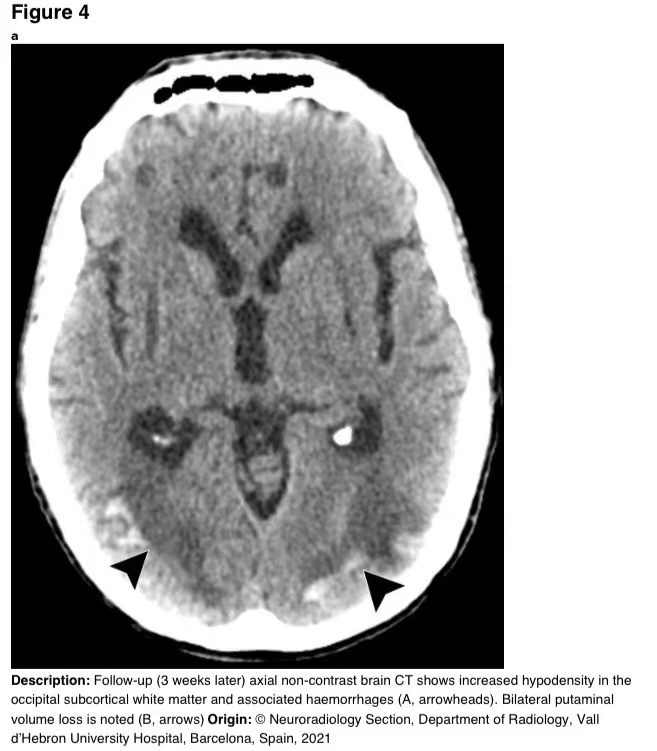

3周后完善的一次新的脑部CT显示,枕下病变的大小增加,并伴有出血性改变(图4)。

图4a

图4 a-b 随访(3周后)轴向CT显示枕下皮质下白质低密度增高及相关出血(A,箭头)。可见双侧壳核体积损失(B,箭头)。